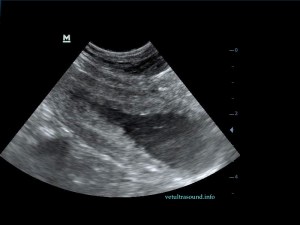

Η πάχυνση του τοιχώματος και η δοκίδωση του βλεννογόνου είναι εμφανής σε όλες τις εικόνες. Πολλές φορές οι λαγόνιοι λεμφαδένες μπορεί να είναι ήπια διογκωμένοι και να έχουν αντιδραστική ηχομορφολογία. Ο έλεγχος με έγχρωμο Doppler του τοιχώματος της άδειας κύστης μπορεί να μας δείξει ροή αίματος στα αγγεία της κύστης. Αντίθετα, είναι πιθανό, όσο η κύστη γεμίζει με ούρο η ροή αίματος να μην είναι ορατή με το Doppler. Αυτό συμβαίνει συχνά στη χρόνια βακτηριακή κυστίτιδα λόγω της ίνωσης του τοιχώματος της ουροδόχου και αυτή είναι μία από τις αιτίες της μη ανταπόκρισης στη θεραπεία. Η συγκεκριμένη παθοφυσιολογία έχει μελετηθεί στον άνθρωπο με την βοήθεια ενδοσκοπικού υπερήχου.

The increase of thickness of the urinary bladder wall and the striation of the mucosa is evident. Inguinal lymphnodes are usually prominent and mildly enlarged. Colour Doppler may reveal the blood flow of the mucosa of the empty urinary bladder, whereas the blood flow in a full bladder appears decreased. This could be because of the fibrosis of the urinary bladder wall and could explain why sometimes chronic conditions like these do not respond well to antibiotics. This pathophysiology has been studied in humans with the use of endoscopic ultrasound.